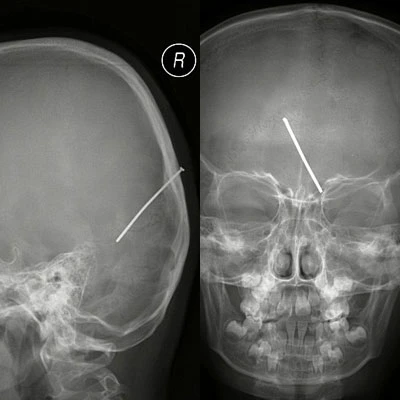

Phim chụp X-quang của bé Mai

Ngay lập tức, bọn trẻ và bé Mai đứng lên ra ngoài. Thật không may, bé Mai đã va phải súng bắn đinh, người thợ giật mình và bóp cò khiến chiếc đinh dài gần 5cm xuyên thẳng vào đầu bé. Bé Mai được bố đưa đến bệnh viện cấp cứu.

Tại đây, khi chụp X- quang cho bé, các bác sỹ thấy chiếc đinh đã găm rất sâu vào hộp sọ của bé. Sau đó, các bác sĩ đã phẫu thuật để lấy chiếc đinh ra. Hiện tại, sức khỏe của bé gái 7 tuổi nay đang tiến triển rất tốt.

Chiếc đinh đã găm vào đầu bé Mai

Bác sỹ Zhao Fuxi cho biết: “May mắn là chiếc đinh không xuyên vào động mạch trong hộp sọ. Nếu động mạch bị vỡ, cô bé có thể đã tử vong vì xuất huyết não.